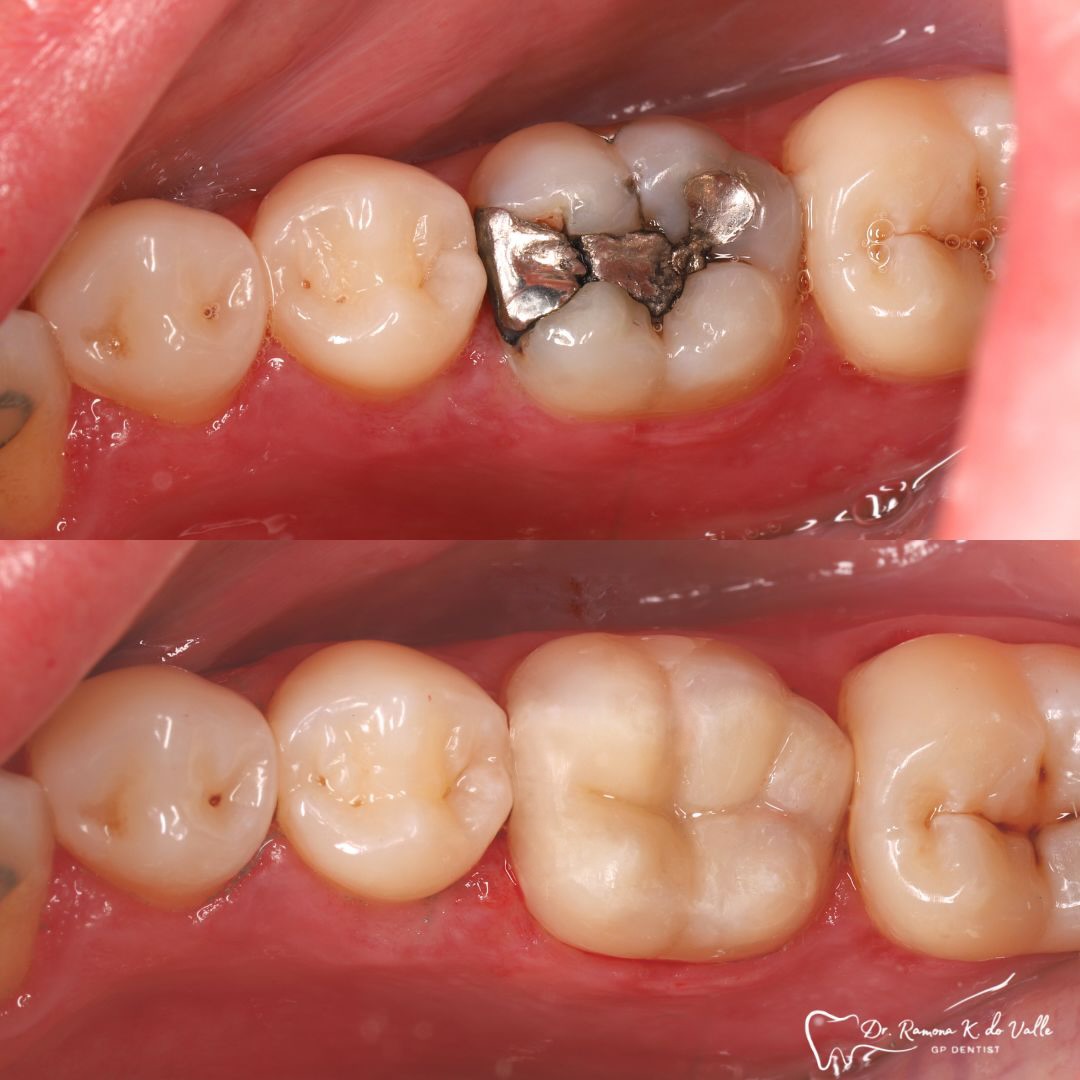

• replacing old metal fillings with a tooth-coloured option

1. Preparation of the Tooth

We remove weakened or decayed tissue and clean the area thoroughly. The goal is to preserve as much healthy structure as possible.

2. Etching and Bonding

A specialised adhesive is applied to create a secure link between your tooth and the composite. Strong bonding prevents leakage, improves longevity, and protects the tooth.

3. Layering the Composite Resin

The tooth-coloured resin is applied in thin layers and shaped carefully to match natural anatomy. For front-tooth work, we may combine several shades for a lifelike result.

4. Curing with Light

Each layer is hardened with a curing light for predictable strength and stability.

5. Final Polishing and Bite Adjustment

We contour and polish the surface to a high gloss and ensure your bite feels natural in all positions.